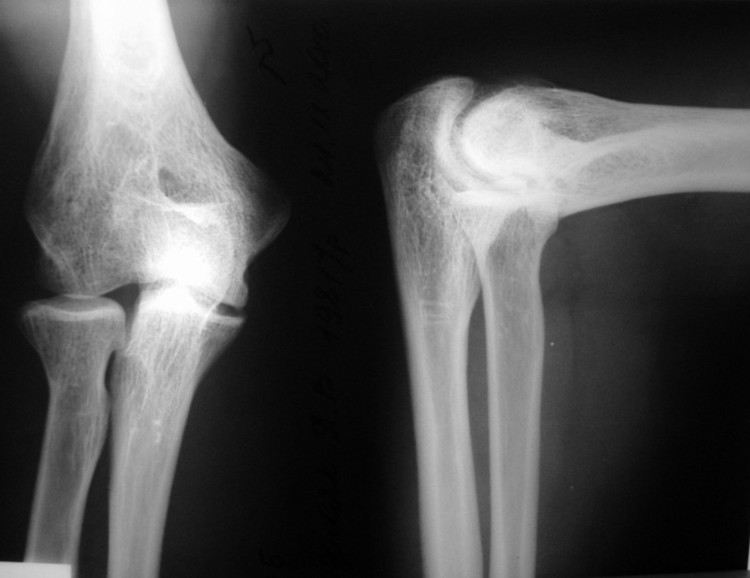

Мужчина, 29 лет. В 15 лет - спортивная травма, закрытый чрезмыщелковый перелом правой плечевой кости со смещением. Лечился консервативно. В настоящее время предъявляет жалобы на ограничение сгибания, повышенную утомляемость.

Объективно: сгибание до 100 гр., разгибание до 170. Неврологических и циркуляторных расстройств нет.

Male, 29 y.o. In age of 15 years he had sport trauma – close transcondylar fracture of the humerus. He had cast fixation and some rehabilitation after it.

Now: complaints for limitation of the flexion, fast weariness.

Flexion: 100 degree, extension – 170. There are no neurological and vascular disorders.

Question: possible surgical treatment for better function of the elbow (opinion, type of surgery, details, prognosis)?